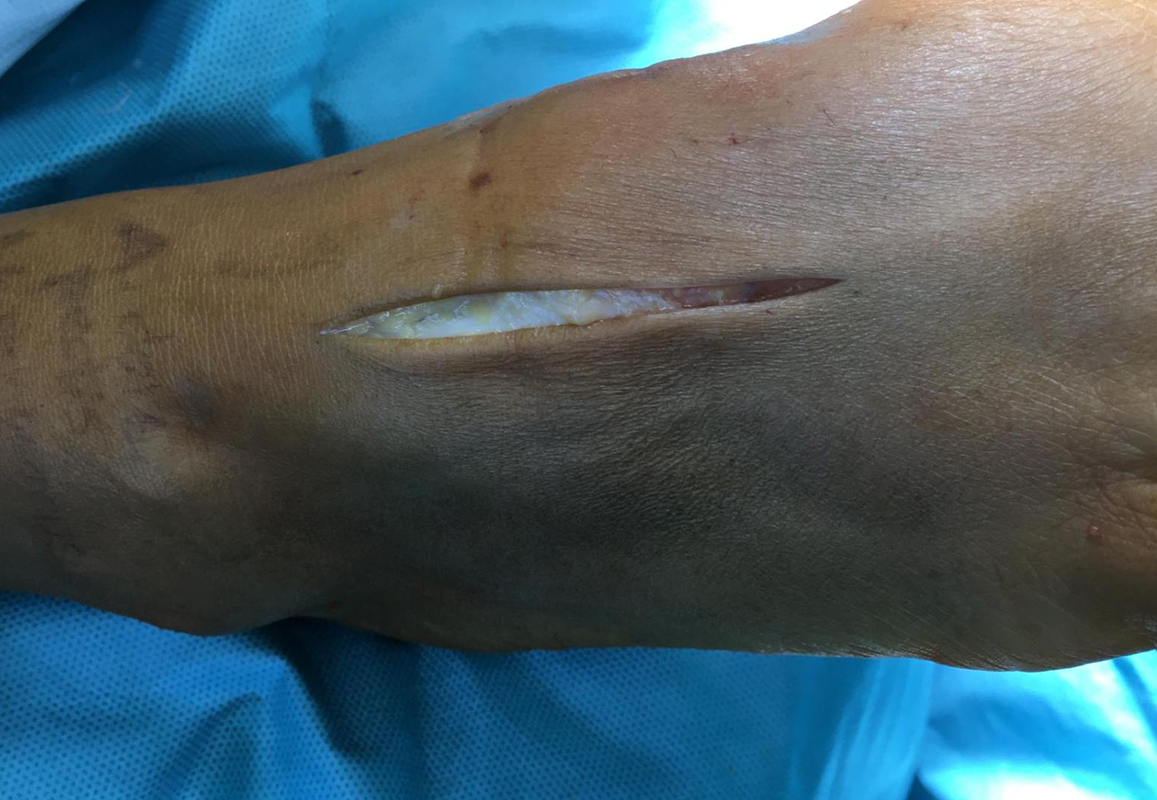

• Hautschnitt lateral / medial der A.dorsalis pedis über dem II./III. Tarsometatarsalgelenk (Abb. 13).

• Mobilisation der Äste des N. peronaeus superficialis Retraktion nach medial oder lateral (Abb. 14).

• In der Tiefe Schutz des Gefäß-Nervenbündels mit A. dorsalis pedis und N. peronaeus profundus. Meist ist es einfacher das Gefäß-Nerven-Bündel nach medial zur retrahieren (Abb. 15).

• Beim postoperativen Wundverschluss ist darauf zu achten die Nerven Strecksehnen nicht durch die subkutanen Nähte zu fixieren. Aufgrund der dünnen Weichteildeckung der Region hat sich in unseren Händen dünnes, resorbierbares Nahtmaterial (zum Beispiel wie Vicryl 2.0) bewährt.

• Postoperative Irritationen des Nervus peronaeus superficialis oder des Nervus peronaeus profundus sind möglich, auch wenn der Nerv nicht iatrogen durchtrennt wurde. Häufig führt allein die Retraktion zu einer in vielen Fällen temporären Funktionsstörung, die sich dann aber über mehrere Monate wieder zurückbildet.